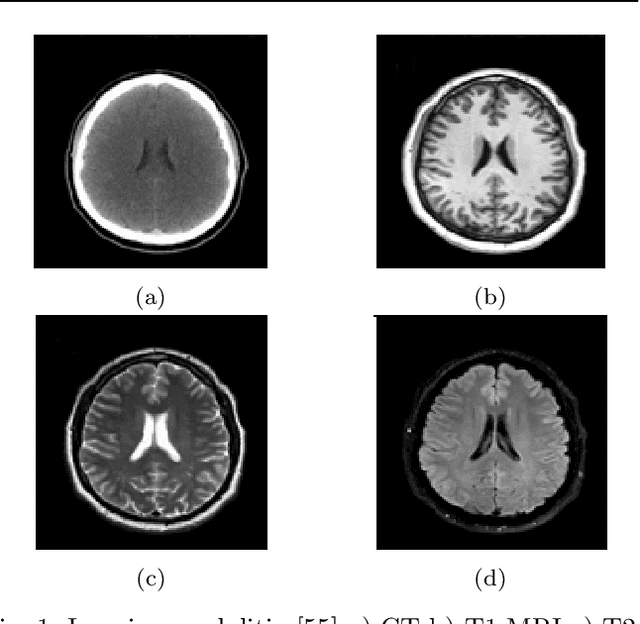

Abstract:Glioma is the most deadly brain tumor with high mortality. Treatment planning by human experts depends on the proper diagnosis of physical symptoms along with Magnetic Resonance(MR) image analysis. Highly variability of a brain tumor in terms of size, shape, location, and a high volume of MR images makes the analysis time-consuming. Automatic segmentation methods achieve a reduction in time with excellent reproducible results. The article aims to survey the advancement of automated methods for Glioma brain tumor segmentation. It is also essential to make an objective evaluation of various models based on the benchmark. Therefore, the 2012 - 2019 BraTS challenges database evaluates state-of-the-art methods. The complexity of tasks under the challenge has grown from segmentation (Task1) to overall survival prediction (Task 2) to uncertainty prediction for classification (Task 3). The paper covers the complete gamut of brain tumor segmentation using handcrafted features to deep neural network models for Task 1. The aim is to showcase a complete change of trends in automated brain tumor models. The paper also covers end to end joint models involving brain tumor segmentation and overall survival prediction. All the methods are probed, and parameters that affect performance are tabulated and analyzed.

Abstract:Brain tumor segmentation intends to delineate tumor tissues from healthy brain tissues. The tumor tissues include necrosis, peritumoral edema, and active tumor. In contrast, healthy brain tissues include white matter, gray matter, and cerebrospinal fluid. The MRI based brain tumor segmentation research is gaining popularity as; 1. It does not irradiate ionized radiation like X-ray or computed tomography imaging. 2. It produces detailed pictures of internal body structures. The MRI scans are input to deep learning-based approaches which are useful for automatic brain tumor segmentation. The features from segments are fed to the classifier which predict the overall survival of the patient. The motive of this paper is to give an extensive overview of state-of-the-art jointly covering brain tumor segmentation and overall survival prediction.